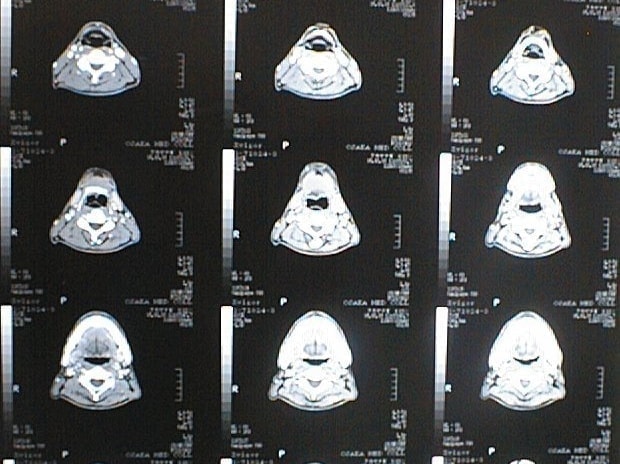

末期がん宣告時と末期がん消滅時の診断画像比較

ここでは、末期がんと宣告された時のCT&MRI画像と、その約3か月後の末期がん消滅時の画像を比較して頂けます。(写真左が「末期がん宣告時の画像」、写真右が「末期がん消滅後の画像」)

MRI画像比較

入院当時MRI画像①

入院3か月後癌消滅MRI画像①

入院当時MRI画像②

入院3か月後癌消滅MRI画像②

入院当時MRI画像③

入院3か月後癌消滅MRI画像③

入院当時MRI画像④

入院3か月後癌消滅MRI画像④